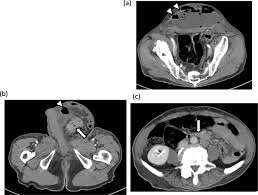

Pdf An Unusual Case Of A Strangulated Right Inguinal Hernia Containing The Sigmoid Colon from i1.rgstatic.net Shelby is very active on our site always there to help others along their way, offering support and answering questions that those who are just starting. It may lead to immediate death, so you have to know symptoms and early warning signs of colon cancer to protect yourself against this disaster. An inguinal hernia containing colorectal cancer is rare but serious and can often present with complications such as perforation. In this condition, pain is caused on the left side of the abdomen but it can also be at the right side, which is quite close to the location of the appendix. Because hernias are more common in men than in women, they can sometimes be an overlooked source of pain for women, according to the society of laparoendoscopic surgeons (sls). A hernia happens anytime a body part pushes into a place where it doesn't belong. A tumor is a solid or cystic mass. The use of synthetic mesh in association with colonic resection did not lead to post operative infection, allowing concomitant treatment of both diseases in elderly, high risk patients.

We therefore conclude that the association between colon cancer and inguinal hernia is mainly coincidental, and the cancer must be suspected on a clinical basis. Less than 1 out of 200 cases of crc is localized within an inguinal hernia 6 . It may lead to immediate death, so you have to know symptoms and early warning signs of colon cancer to protect yourself against this disaster. Colon cancer is a very critical issue and maybe one of the causes of sudden death in young men, women and elderly. I performed an scope examination of her esophagus and confronted a huge cancer occupying the lower portion of her esophagus. The use of synthetic mesh in association with colonic resection did not lead to post operative infection, allowing concomitant treatment of both diseases in elderly, high risk patients. In the region of the inguinal canal, where most hernias occur, there are lymph nodes that can enlarge from infectious or malignancies, and can be mistaken for a hernia. When a hernia meets cancer. A tumor is a solid or cystic mass. A female patient came to see me with some difficulty swallowing, a very routine issue for a gastroenterologist. When colon cancer is detected in its early stages, there may be no symptoms present at all. Typically, patients with ventral hernias describe mild pain, aching or a pressure sensation at the site of the hernia. As detailed in the risk factors, acid reflux caused by hiatal hernia is one of the main cause of esophageal cancer.

From Inguinal Hernias To Spermatic Cord Lipomas Pearls Pitfalls And Mimics Of Abdominal And Pelvic Hernias Radiographics from pubs.rsna.org The discomfort worsens with any activity that puts a strain on the abdomen, such as heavy lifting, running. Cancer misdiagnosis can have devastating results for the patient. It may lead to immediate death, so you have to know symptoms and early warning signs of colon cancer to protect yourself against this disaster. Colon cancer may be diagnosed with the following colon cancer testing: A hernia happens anytime a body part pushes into a place where it doesn't belong. Symptoms of hiatal hernia include: Typically, patients with ventral hernias describe mild pain, aching or a pressure sensation at the site of the hernia. In the region of the inguinal canal, where most hernias occur, there are lymph nodes that can enlarge from infectious or malignancies, and can be mistaken for a hernia.

Although still considered rare, adenocarcinoma of the esophagus, the most common form of esophageal cancer, is one of the. Since a hiatal hernia often exhibits the same symptoms as other conditions, it can be easily mistaken for something else entirely. De caestecker discusses hernia symptoms and what they might be mistaken for. Initial common symptoms in patients presenting with colon cancer are abdominal pain, change in bowel habits, melaena, and general weakness 5 . Colonoscopy, a procedure which involves a flexible tube with an attached video camera. Some of the other medical conditions that can be confused with appendicitis include: In cases where cancer is not identified or mistaken for another disease, patients may miss a critical window for treatment. As detailed in the risk factors, acid reflux caused by hiatal hernia is one of the main cause of esophageal cancer. Many conditions can cause hip pain, and cancer is one of them. An inguinal hernia containing colorectal cancer is rare but serious and can often present with complications such as perforation. Less than 1 out of 200 cases of crc is localized within an inguinal hernia 6 . Do not hesitate to consult your cancer doctor immediately and visit a colon cancer center if you suffer from any of these warning signs. She is an endometrial cancer survivor and is starting to get compfortable with the idea of being a survivor.